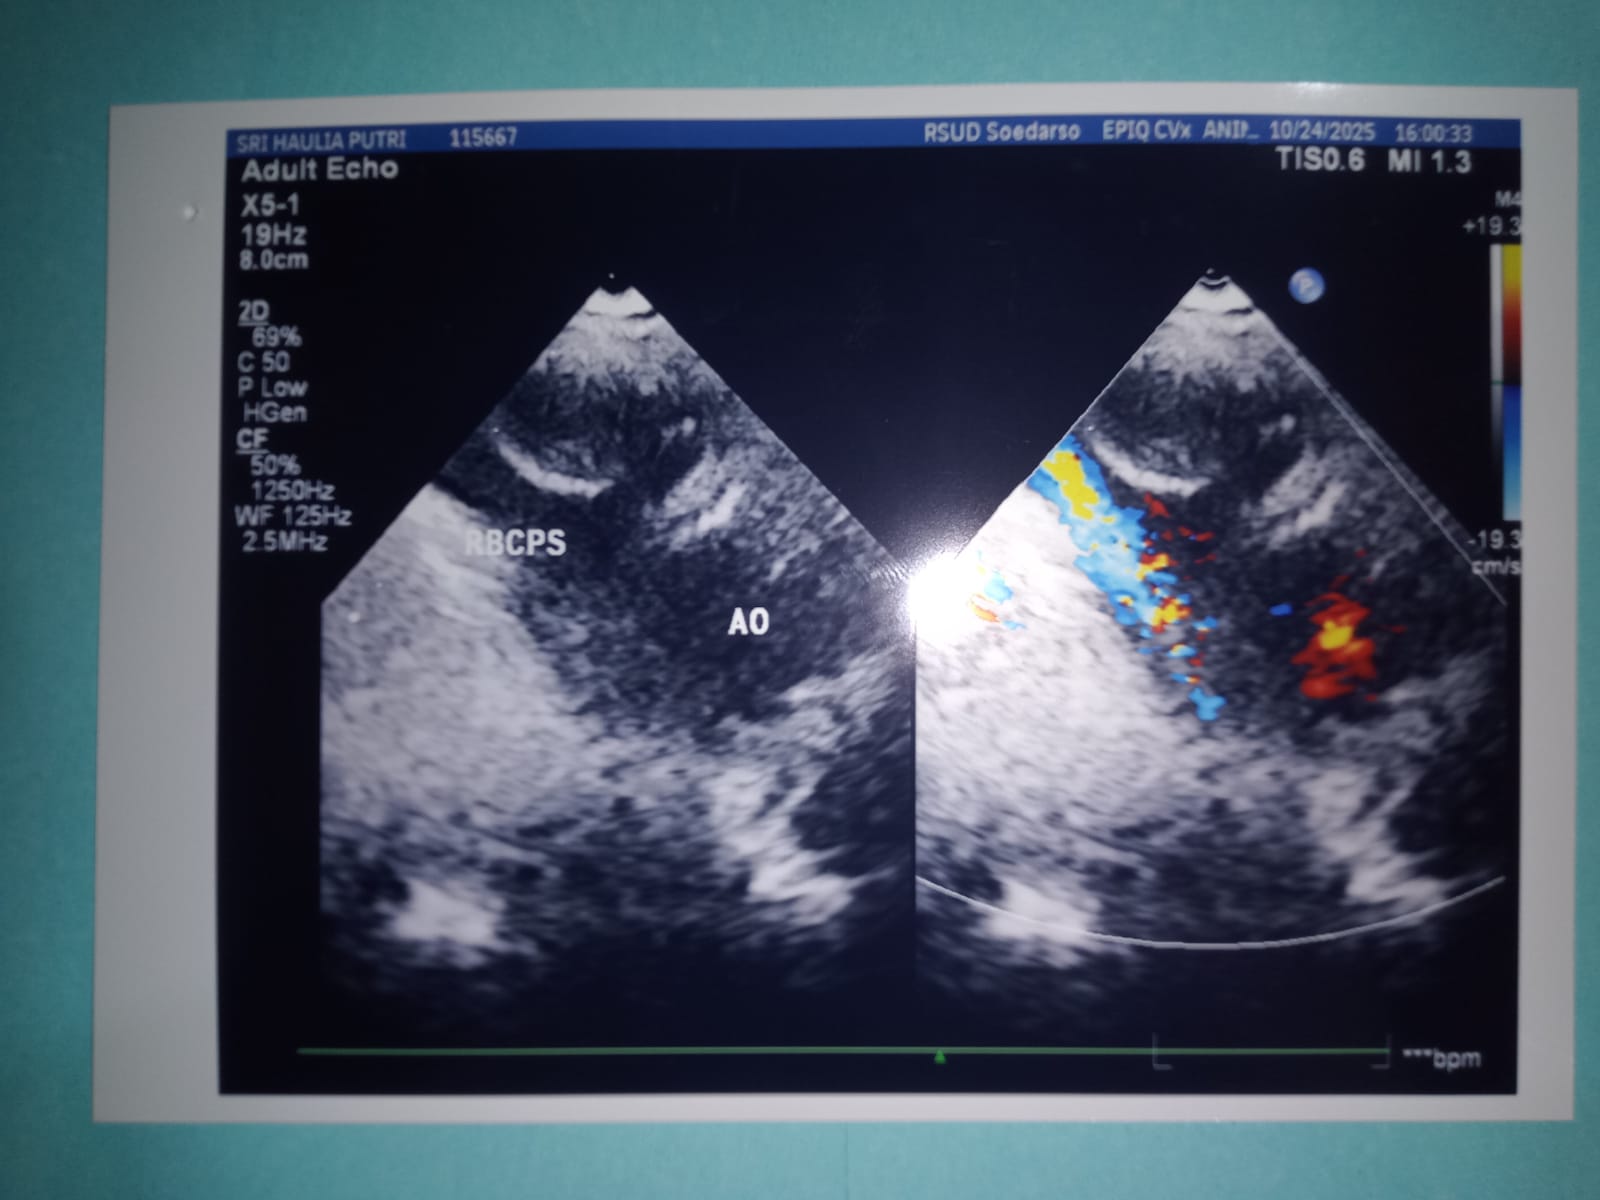

Awalnya, kondisi Sri menurun karena mengalami batuk terus-menerus disertai muntah berkali-kali hingga mengeluarkan darah, serta demam tinggi. Kami pun segera membawanya ke IGD RSUD Pontianak untuk mendapatkan penanganan lebih lanjut. Sri langsung diberikan infus dan oksigen. Dari hasil pemeriksaan rontgen dan USG jantung, dokter menyatakan bahwa Sri mengalami infeksi pada paru-paru, lambung, dan katup jantung.